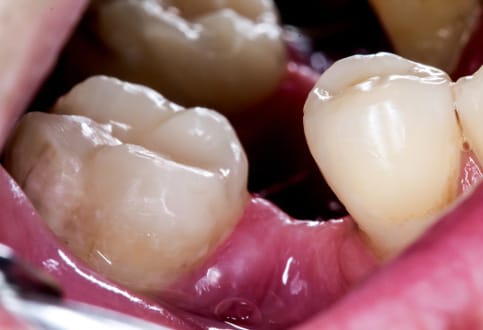

Trồng răng Implant là giải pháp phục hồi răng mất hiện đại, mang lại khả năng ăn nhai gần như răng thật và độ bền lâu dài. Tuy nhiên, một trong những câu hỏi được quan tâm nhiều nhất là: Giá trồng răng Implant tại TP.HCM bao nhiêu?